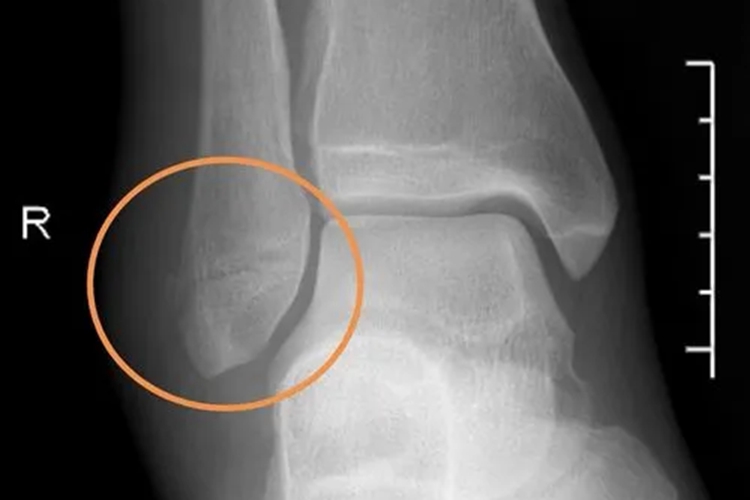

腓骨下端骨折的临床表现为伤肢疼痛并出现肿胀、畸形、压痛等情况,有时可出现硬性隆起。X线片上的改变出现较晚,一般在2周后可出现不太清晰的骨折线,呈一骨质疏松带或骨质致密带,继而陆续出现骨膜性新骨形成和骨痂生长。

腓骨下端骨折的患者需在医生指导下治疗,对于无移位的腓骨下端骨折,可采取手法复位外固定;若发生移位、无法手法复位外固定或固定失败者,可选择开放性复位内固定治疗。